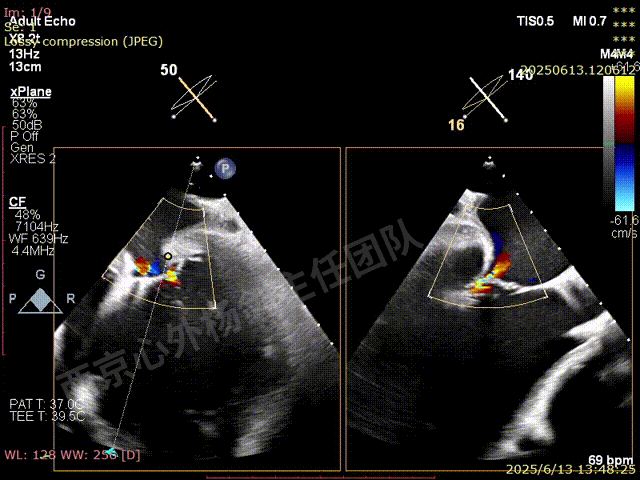

夹子关闭后检查夹子两侧反流

第一枚XTW释放后评估,外侧反流基本消失,内侧仍然有中度以上反流

第二枚XT于第一枚夹子内侧瓣上调整

第二枚XT关闭后评估,trace

二尖瓣平均跨瓣压差1mmHg

释放后评估,反流降至1+,组织桥稳定